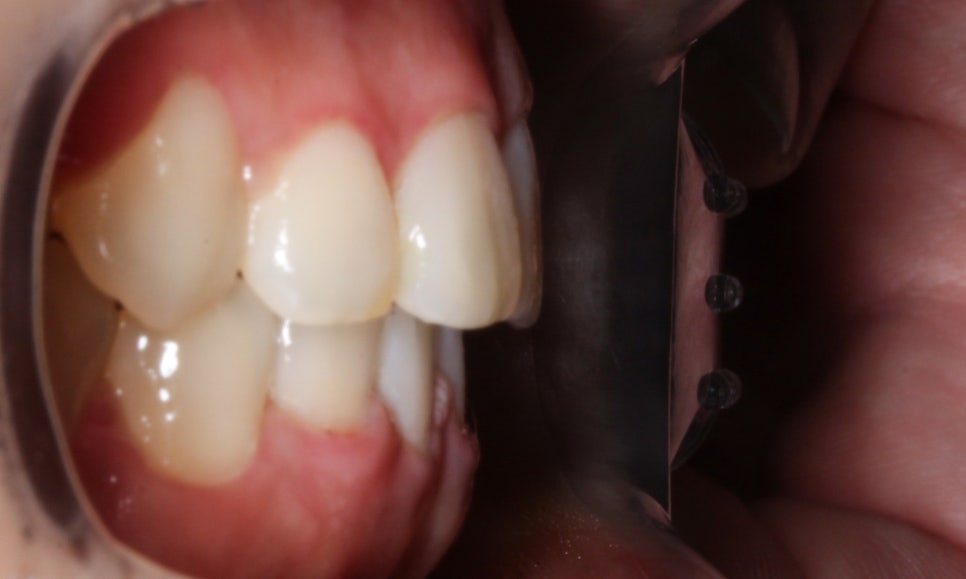

좌우의 교합평면을 보시면 교정 전

덧니로 인해 상악의 high canine가

도드라져 보였는데요,

교정 후 기준치가 되는 송곳니의 위치가

바르게 교정되면서 측면에서 본 치아의 배열이

가지런하게 바뀐 것을 확인할 수 있습니다.